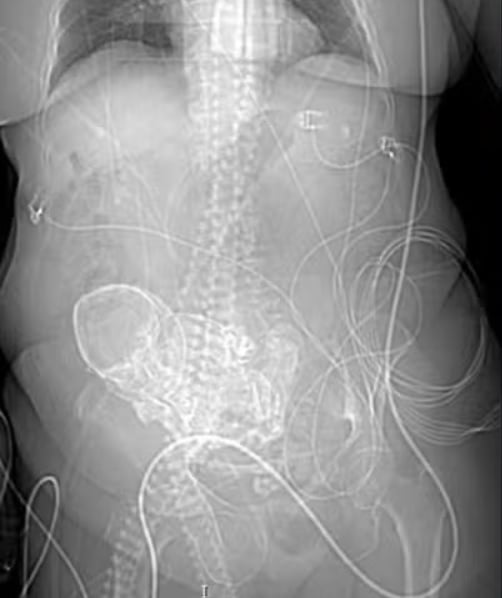

Mulher passa mais de 50 anos com feto calcificado na barriga